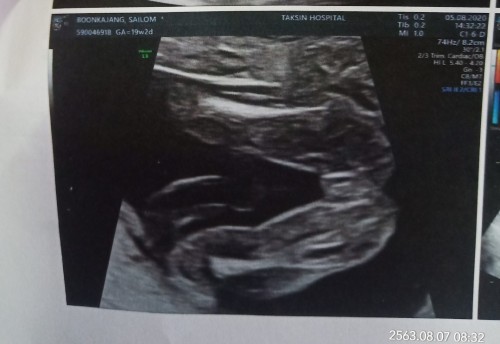

หมอบอกหนูเป็นผู้หญิงจ้า #ซาว21w